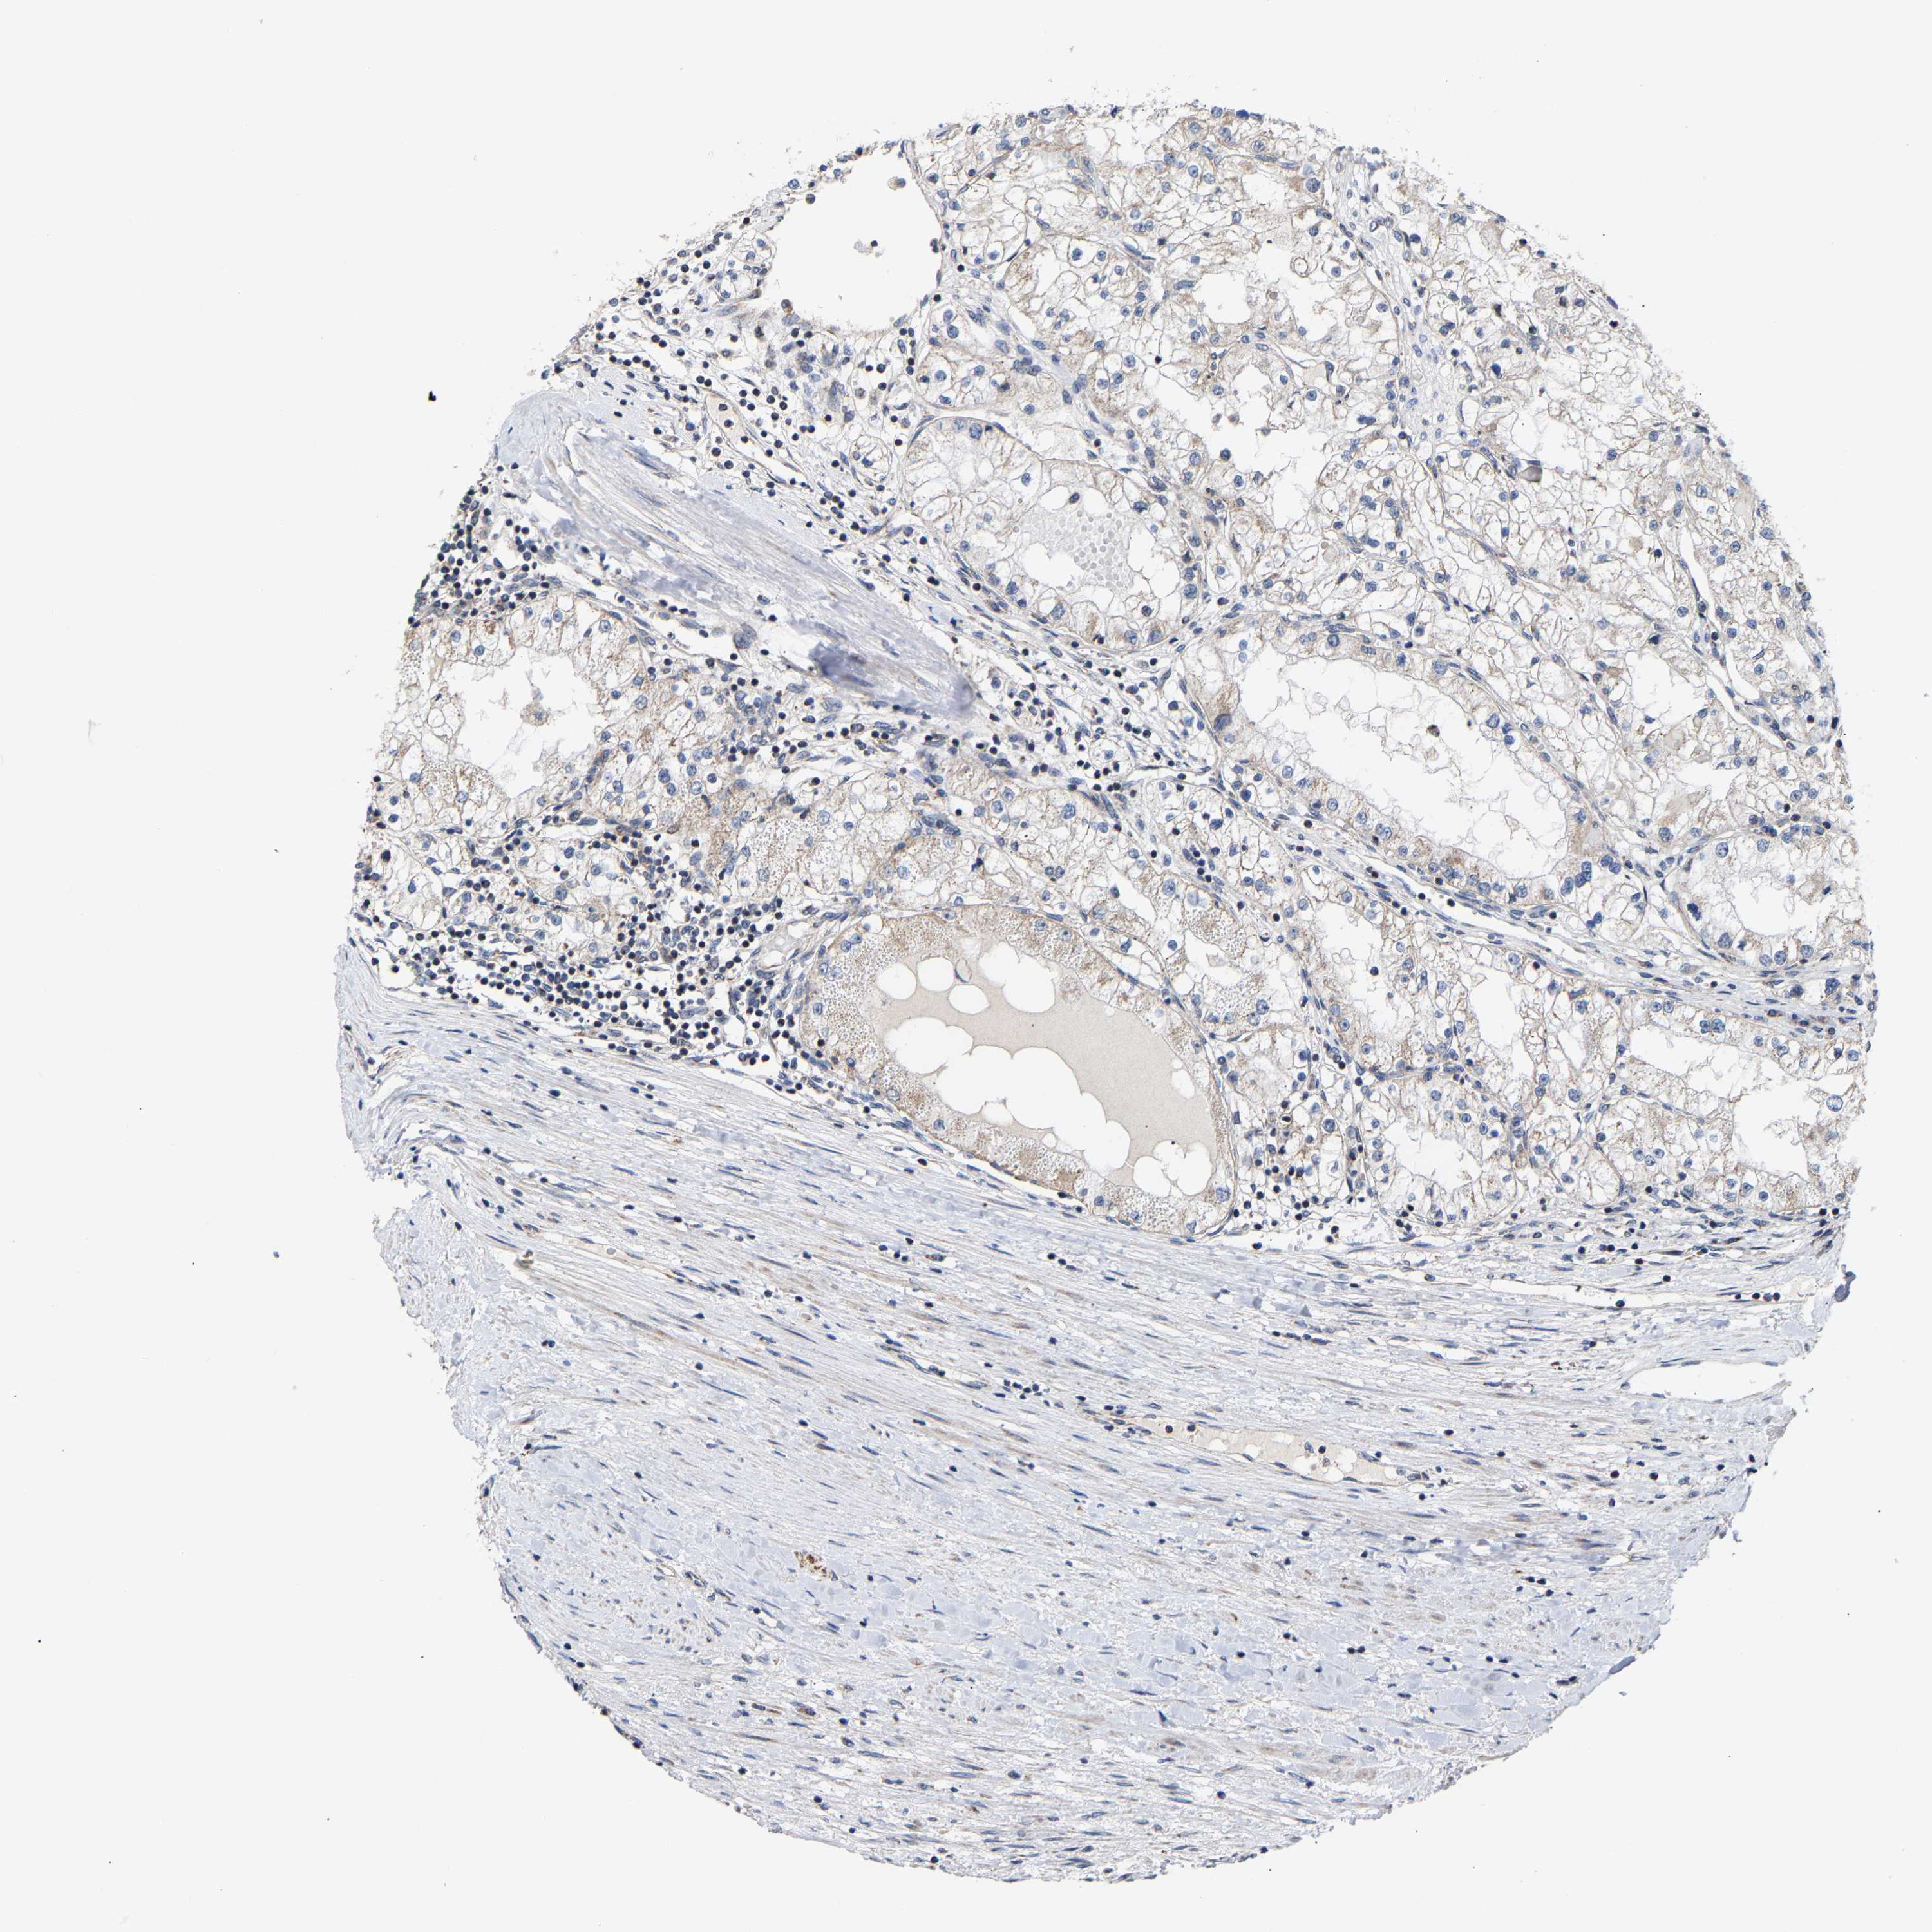

KIDNEY RENAL PAPILLARY CELL CARCINOMA (TCGA) - Interactive survival scatter ploti

The Survival Scatter plot shows the clinical status (i.e. dead or alive) for all individuals in the patient cohort, based on the same data that underlies the corresponding Kaplan-Meier plots. Patients that are alive at last time for follow-up are shown in blue and patients who have died during the study are shown in red.

The x-axis shows the expression levels (FPKM) of the investigated gene in the tumor tissue at the time of diagnosis. The y-axis shows the follow-up time after diagnosis (years). Both axes are complimented with kernel density curves demonstrating the data density over the axes. The top density plot shows the expression levels (FPKM) distribution among dead (red) and alive patients (blue). The right density plot shows the data density of the survived years of dead patients with high and low expression levels respectively, stratified using the cutoff indicated by the vertical dashed line through the Survival Scatter plot. This cutoff is automatically defined based on the FPKM cutoff that minimizes the p-score. The cutoff can be changed by dragging the vertical line or by entering a cutoff value in the square labeled "Current cut-off".

Under the Survival Scatter plot the p-score landscape (black curve; left axis) is shown together with dead median separation (red curve; right axis). Dead median separation is the difference in median mRNA expression between patients who have died with high and low expression, respectively. It is calculated as follows: median FPKM expression of dead patients with high expression - median FPKM expression of dead patients with low expression. This is intended to aid the user in visually exploring custom cutoffs and the associated p-scores and dead median separation.

Individual patient data is displayed and can be filtered by clicking on one or more of the category buttons on the top of the page. Categories describing expression level and patient information include: high, low, alive, dead, female, male and tumor stages. The scale of the x-axis can be toggled between linear and log-scale by clicking on the "x log" button. Mouse-over function shows TCGA ID, patient information and mRNA expression (FPKM) for each patient.

& Survival analysisi

Kaplan-Meier plots summarize results from analysis of correlation between mRNA expression level and patient survival. Patients were divided based on level of expression into one of the two groups "low" (under cut off) or "high" (over cut off). X-axis shows time for survival (years) and y-axis shows the probability of survival, where 1.0 corresponds to 100 percent.

PCNT is not prognostic in Kidney Renal Papillary Cell Carcinoma (TCGA)

Best expression cut offi

Based on the FPKM value of each gene, patients were classified into two groups and association between prognosis (survival) and gene expression (FPKM) was examined. The best expression cut-off refers the FPKM value that yields maximal difference with regard to survival between the two groups at the lowest log-rank P-value. Best expression cut-off was selected based on survival analysis .

When clicking on this number, the vertical dashed line indicating cut-off, the interactive survival plot, and the Kaplan-Meier curve will be adjusted to show results based on the best expression cut-off.

: 5.44